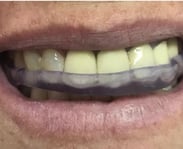

PLACA DE BRUXISMO

Placa de bruxismo: proteção para os dentes, alívio para as ATMs e relaxamento para os músculos mastigatórios

Escaneamento intra oral

Desenho Digital da placa

Impressão 3D da placa

Ajuste da placa no modelo

Entrega da placa